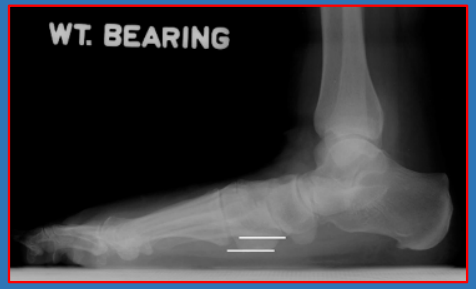

13 后足—跟骨倾斜角

跟骨倾斜角calcaneal pitch angle/heel pitch angle,HPA/calcaneal inclination:负重侧位片中跟骨下表面最低两点连线与水平线的夹角

正常范围:10~30°。对足弓判断较为敏感,特异性也较高<10°平足,>30°弓形足